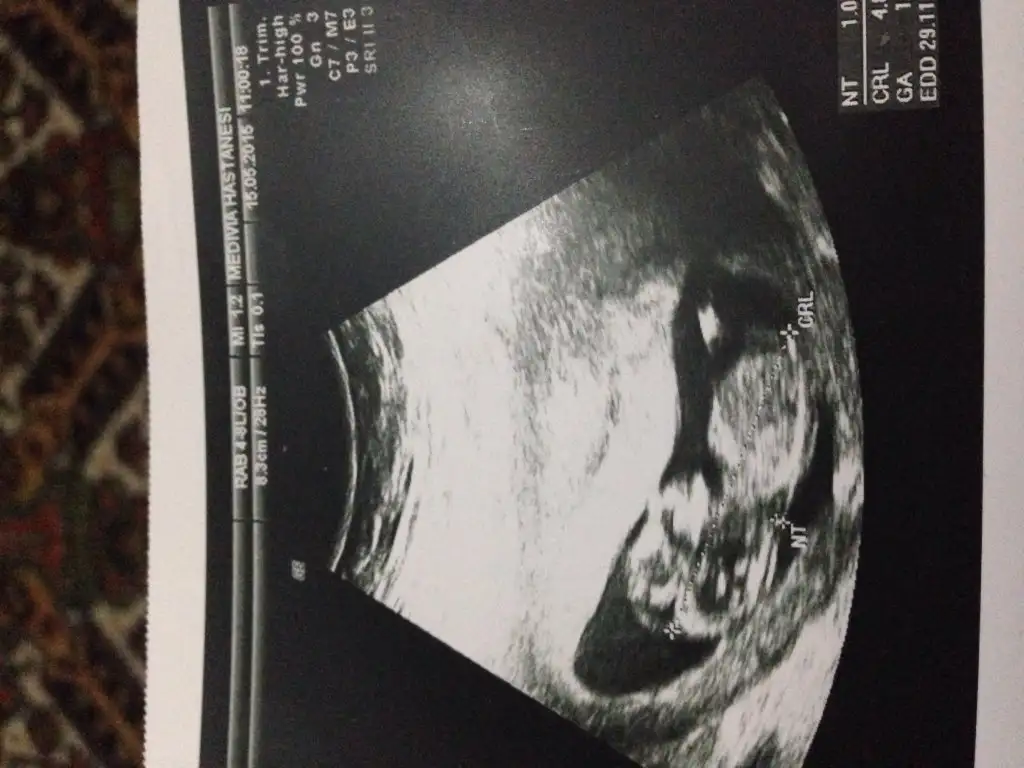

sağol canım ağzına sağlıkCanım seninkini erkek bebeğe benzettim ikinci Fotoğrafın alt kısmında bir şeyler var gibi. Ama bebek arkasını dönmüş bu teori için yandan ya da önden olması lazım Fotoğrafın.

Canım nub teorisi için 12-13 haftalar en ideal haftalar. Kese teorisine koy istersen ama bence o teori nub teorisi gibi bilimsel değil.

Tamam canım inşAllah. Ikili teste gittiğinde Bebeğin yandan fotoğrafını iste. O hafta en uygun zaman.Cevabin için tesekkur ederim canım kismet olursa 4 hafta sonra koyarım o zmn yorumlarsin insallah